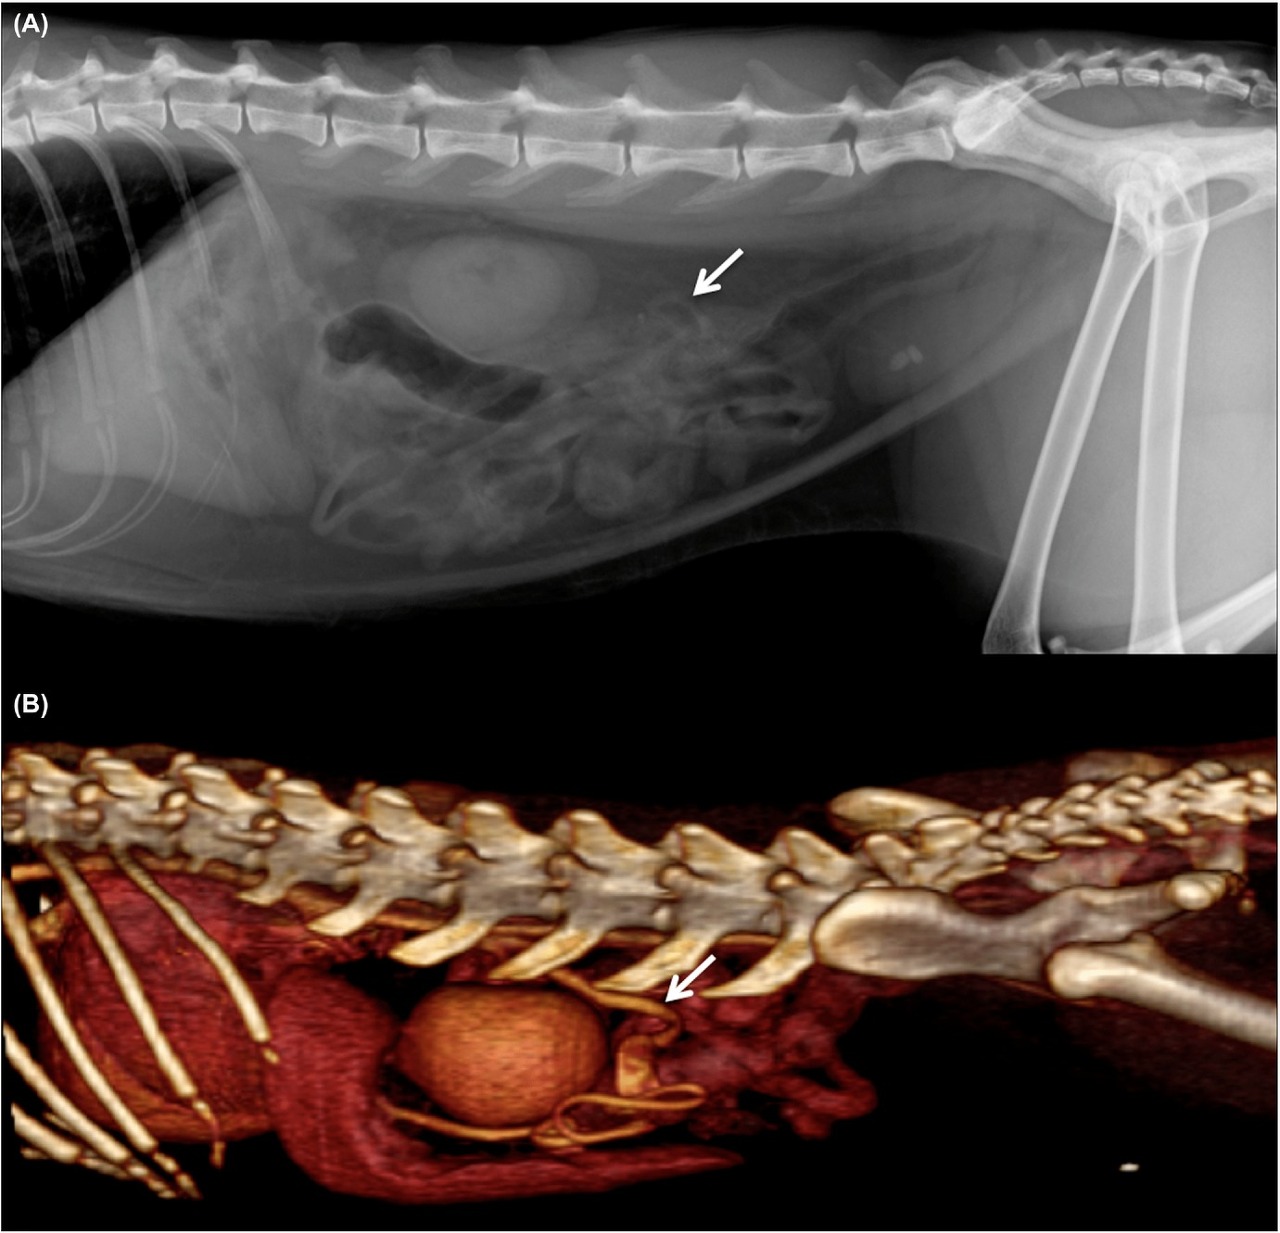

방사선 검사상의 소견은

이런 양상인데